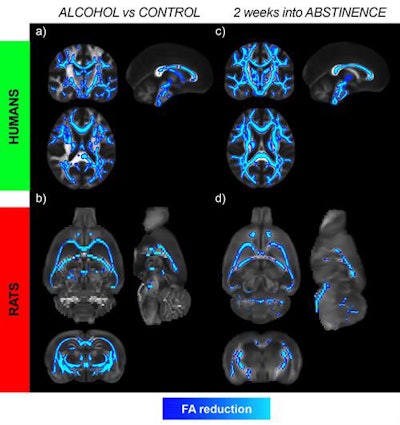

Microstructural changes in white matter in human alcoholics (a) and alcohol-exposed rats (b) were measured using DTI-MRI to provide an index of microstructural integrity. The changes further progress after two weeks of abstinence in both species, as seen in (c) the humans and (d) rats. The results challenge the current view that alterations in the brain begin to normalize immediately after quitting alcohol and indicate that persistent brain deficits can occur much earlier than is currently believed. Images courtesy of Silvia De Santis, PhD.There is no doubt about the harmful effects of alcohol, and the detection of alcohol-induced brain damage is a high priority. However, there are no reliable diagnostic markers to characterize brain damage due to alcohol, the researchers noted, especially at the beginning of abstinence -- a time when the chance of relapse to drinking is high.

When the researchers reviewed the DTI results during the weeks of abstinence, they observed widespread microstructural abnormalities, such as reduced fractional anisotropy and axial diffusivity and increased mean and radial diffusivity, among men with alcohol use disorder, compared with the controls. The differences were most notable in the white-matter tracts of the corpus callosum and fornix/fimbria. That finding alone contradicts the conventional idea that the brain begins to return to normal function immediately after the start of abstinence.